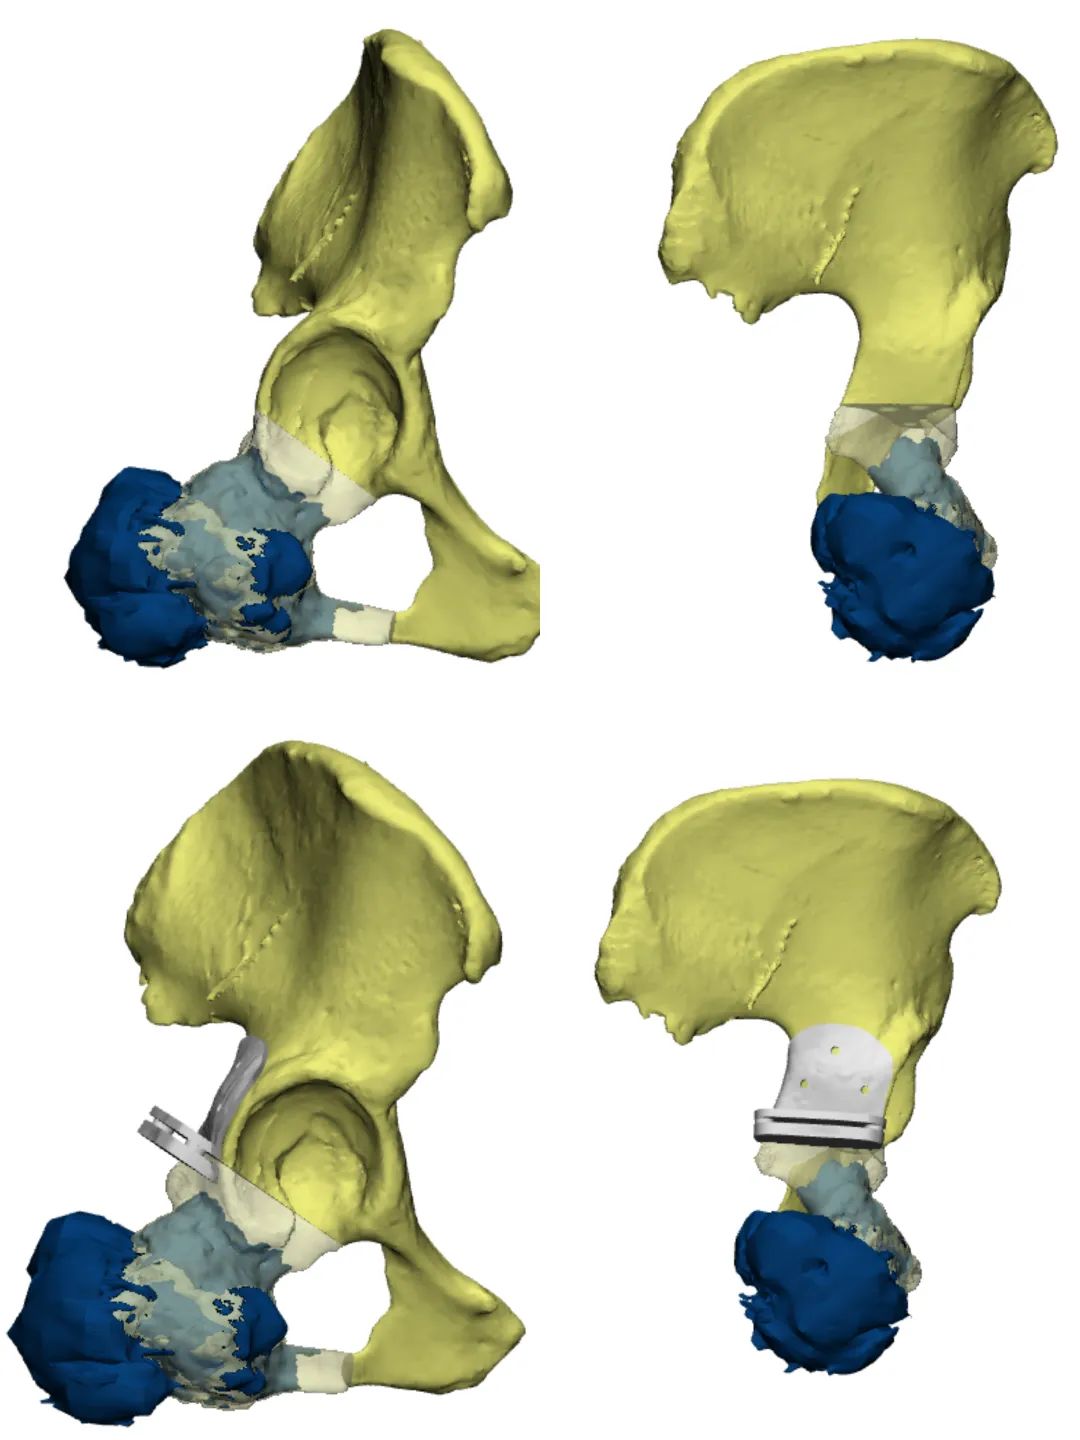

杨团民主任医师带领团队反复讨论,结合患者的病理结果,通过术前数字化模拟,决定在肿瘤与髋臼侧,距离肿瘤上缘约1cm处截骨,切除约1/4髋臼,即右侧骨盆部分II区+III区切除,在肿瘤完整切除的情况下,尽可能多的保留患者髋臼部位,提高了疗效也改善预后。

(术前数字化模拟肿瘤大小及部位、3D打印设计导板辅助术中截骨,手术效果更精确)

(如图所示三者高度吻合,手术按计划完成)